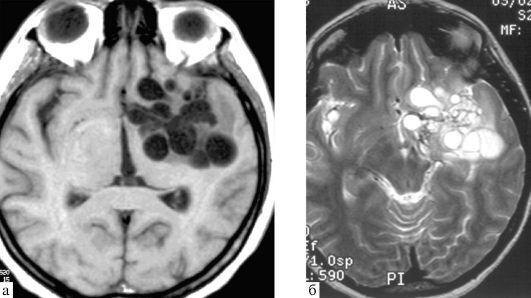

«Вот эти огромные черные пятна и есть те самые кисты, которые заняли всю правую долю моей печени, — показывая снимок КТ, говорит художница. — Самая большая киста была объемом целый литр. Внутри нее были личинки. Поэтому трогать этот пузырь нельзя было. Если хоть одна личинка попадет в кровоток, то зараза распространится повсюду».